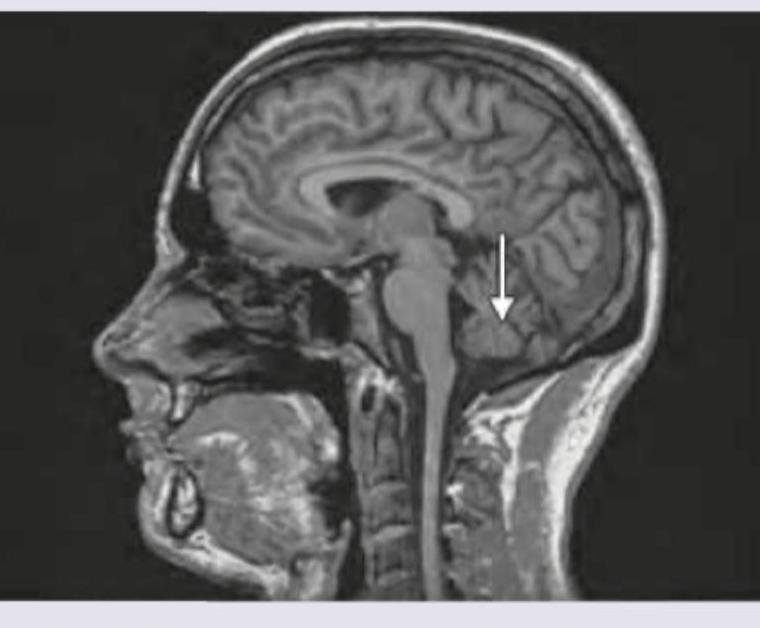

Identify the structure shown. (Recent NEET Pattern 2019)

Explanation: ***Cerebellum*** - The arrow in the sagittal MRI view points to the posterior cranial fossa, where the **cerebellum** is located, characterized by its distinctive folia and fissures. - The cerebellum is critical for **motor control**, balance, coordination, and learning motor skills. *Pons* - The **pons** is located anterior to the cerebellum, appearing as a prominent bulge on the brainstem, superior to the medulla. - It primarily acts as a communication bridge between the **cerebrum and cerebellum** and contains nuclei important for sleep, respiration, and bladder control. *Medulla* - The **medulla oblongata** is the lowest part of the brainstem, continuous with the spinal cord, situated inferior to the pons. - It contains vital autonomic centers for **cardiac, respiratory, and vasomotor functions**. *Occipital cortex* - The **occipital cortex** is part of the cerebrum, located at the posterior pole of the brain, superior to the cerebellum, and is responsible for **visual processing**. - It is identifiable by its characteristic gyri and sulci, distinctly different from the highly folded cerebellar folia.